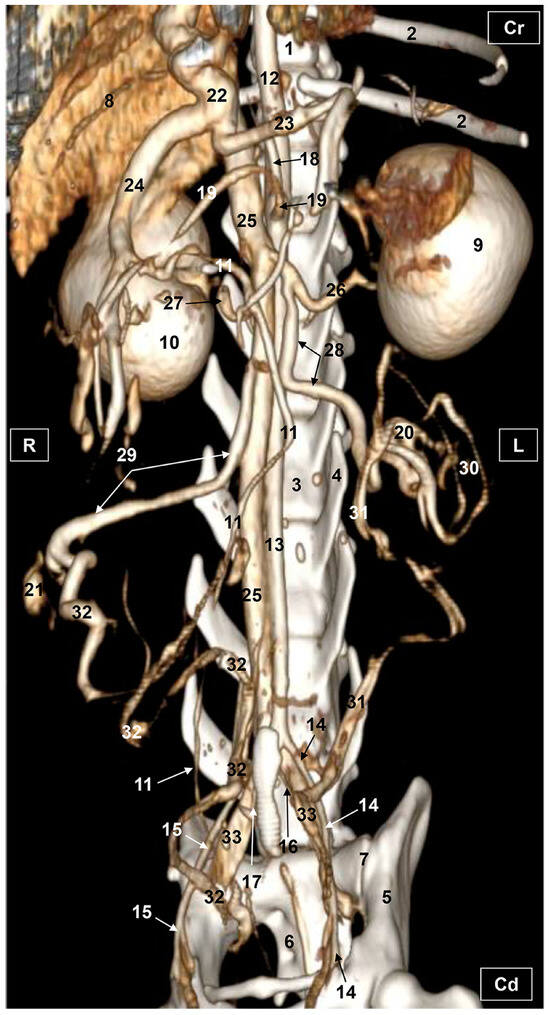

3.2. Computed Tomography Angiography and 3D Printing

3.2.1. Arterial System

3.2.2. Venous System